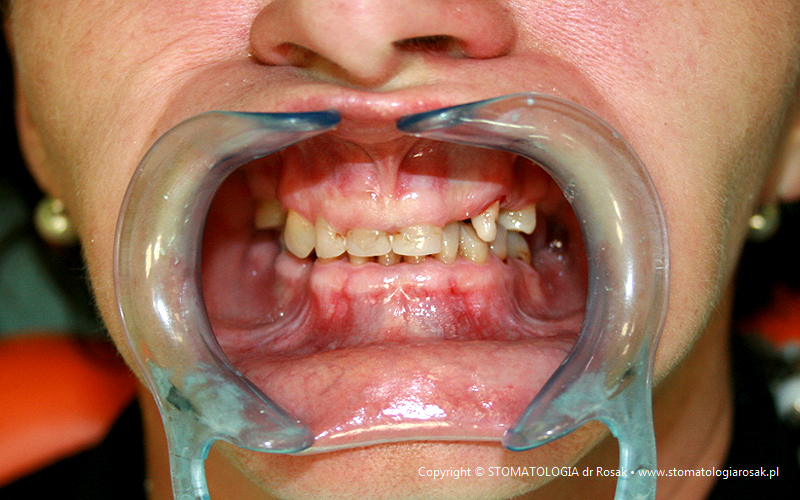

9. Pacjent lat 57- zgłosił się celem usunięcia zniszczonych zębów i wykonania protez ruchomych całkowitych.

NIE USUNĘLIŚMY - ANI JEDNEGO ZĘBA!!!

| 9a. Przed leczeniem |

9b. Gotowe korony i mosty porcelanowe na górze

(trójkę górną prawą pacjent zażyczył sobie nie korygować)

oraz w żuchwie tzw. czapeczki pokrywające oraz zatrzaski kulowe dla lepszego utrzymania protezy ruchomej dolnej |

| 9c. Gotowa praca |